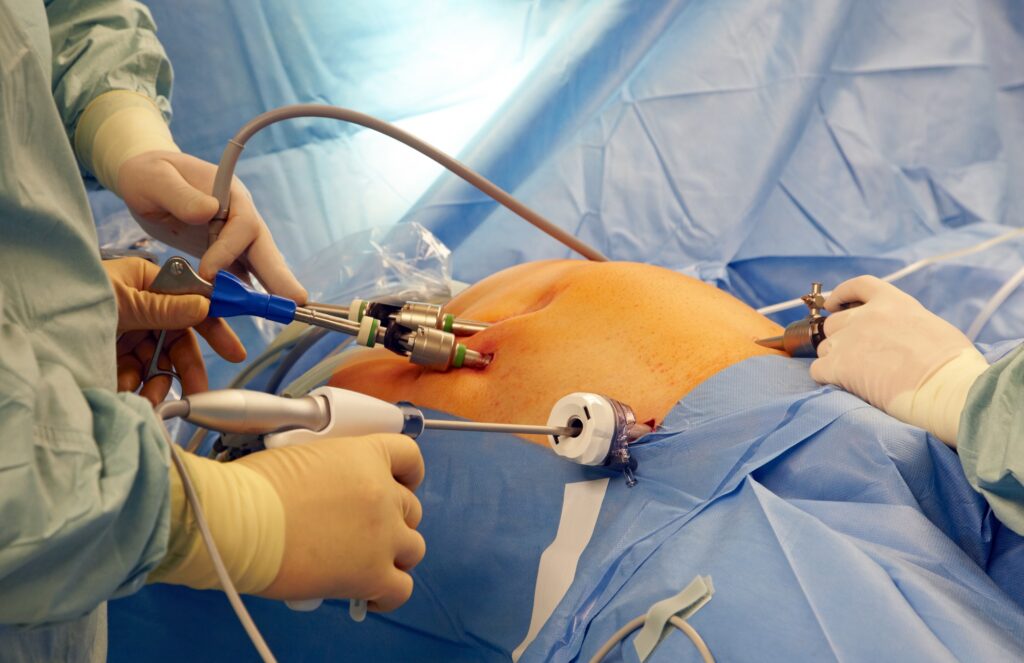

Dr. Lokendra Kumar General and Laparoscopic Surgeon with special interest in Cancer surgery, Gastro ( G.I) surgery and Minimal invasive surgery, More than 14 years of experience in the field expertise in Laparoscopic appendix surgery, Laparoscopic gall bladder surgery, Laparoscopic hernia surgery, Laparoscopic Gastro Surgery, Laparoscopic abdominal surgery, colorectal surgery, thyroid Surgery, varicose veins Surgery, Stone surgery, piles surgery, fistula and fissure Surgery.